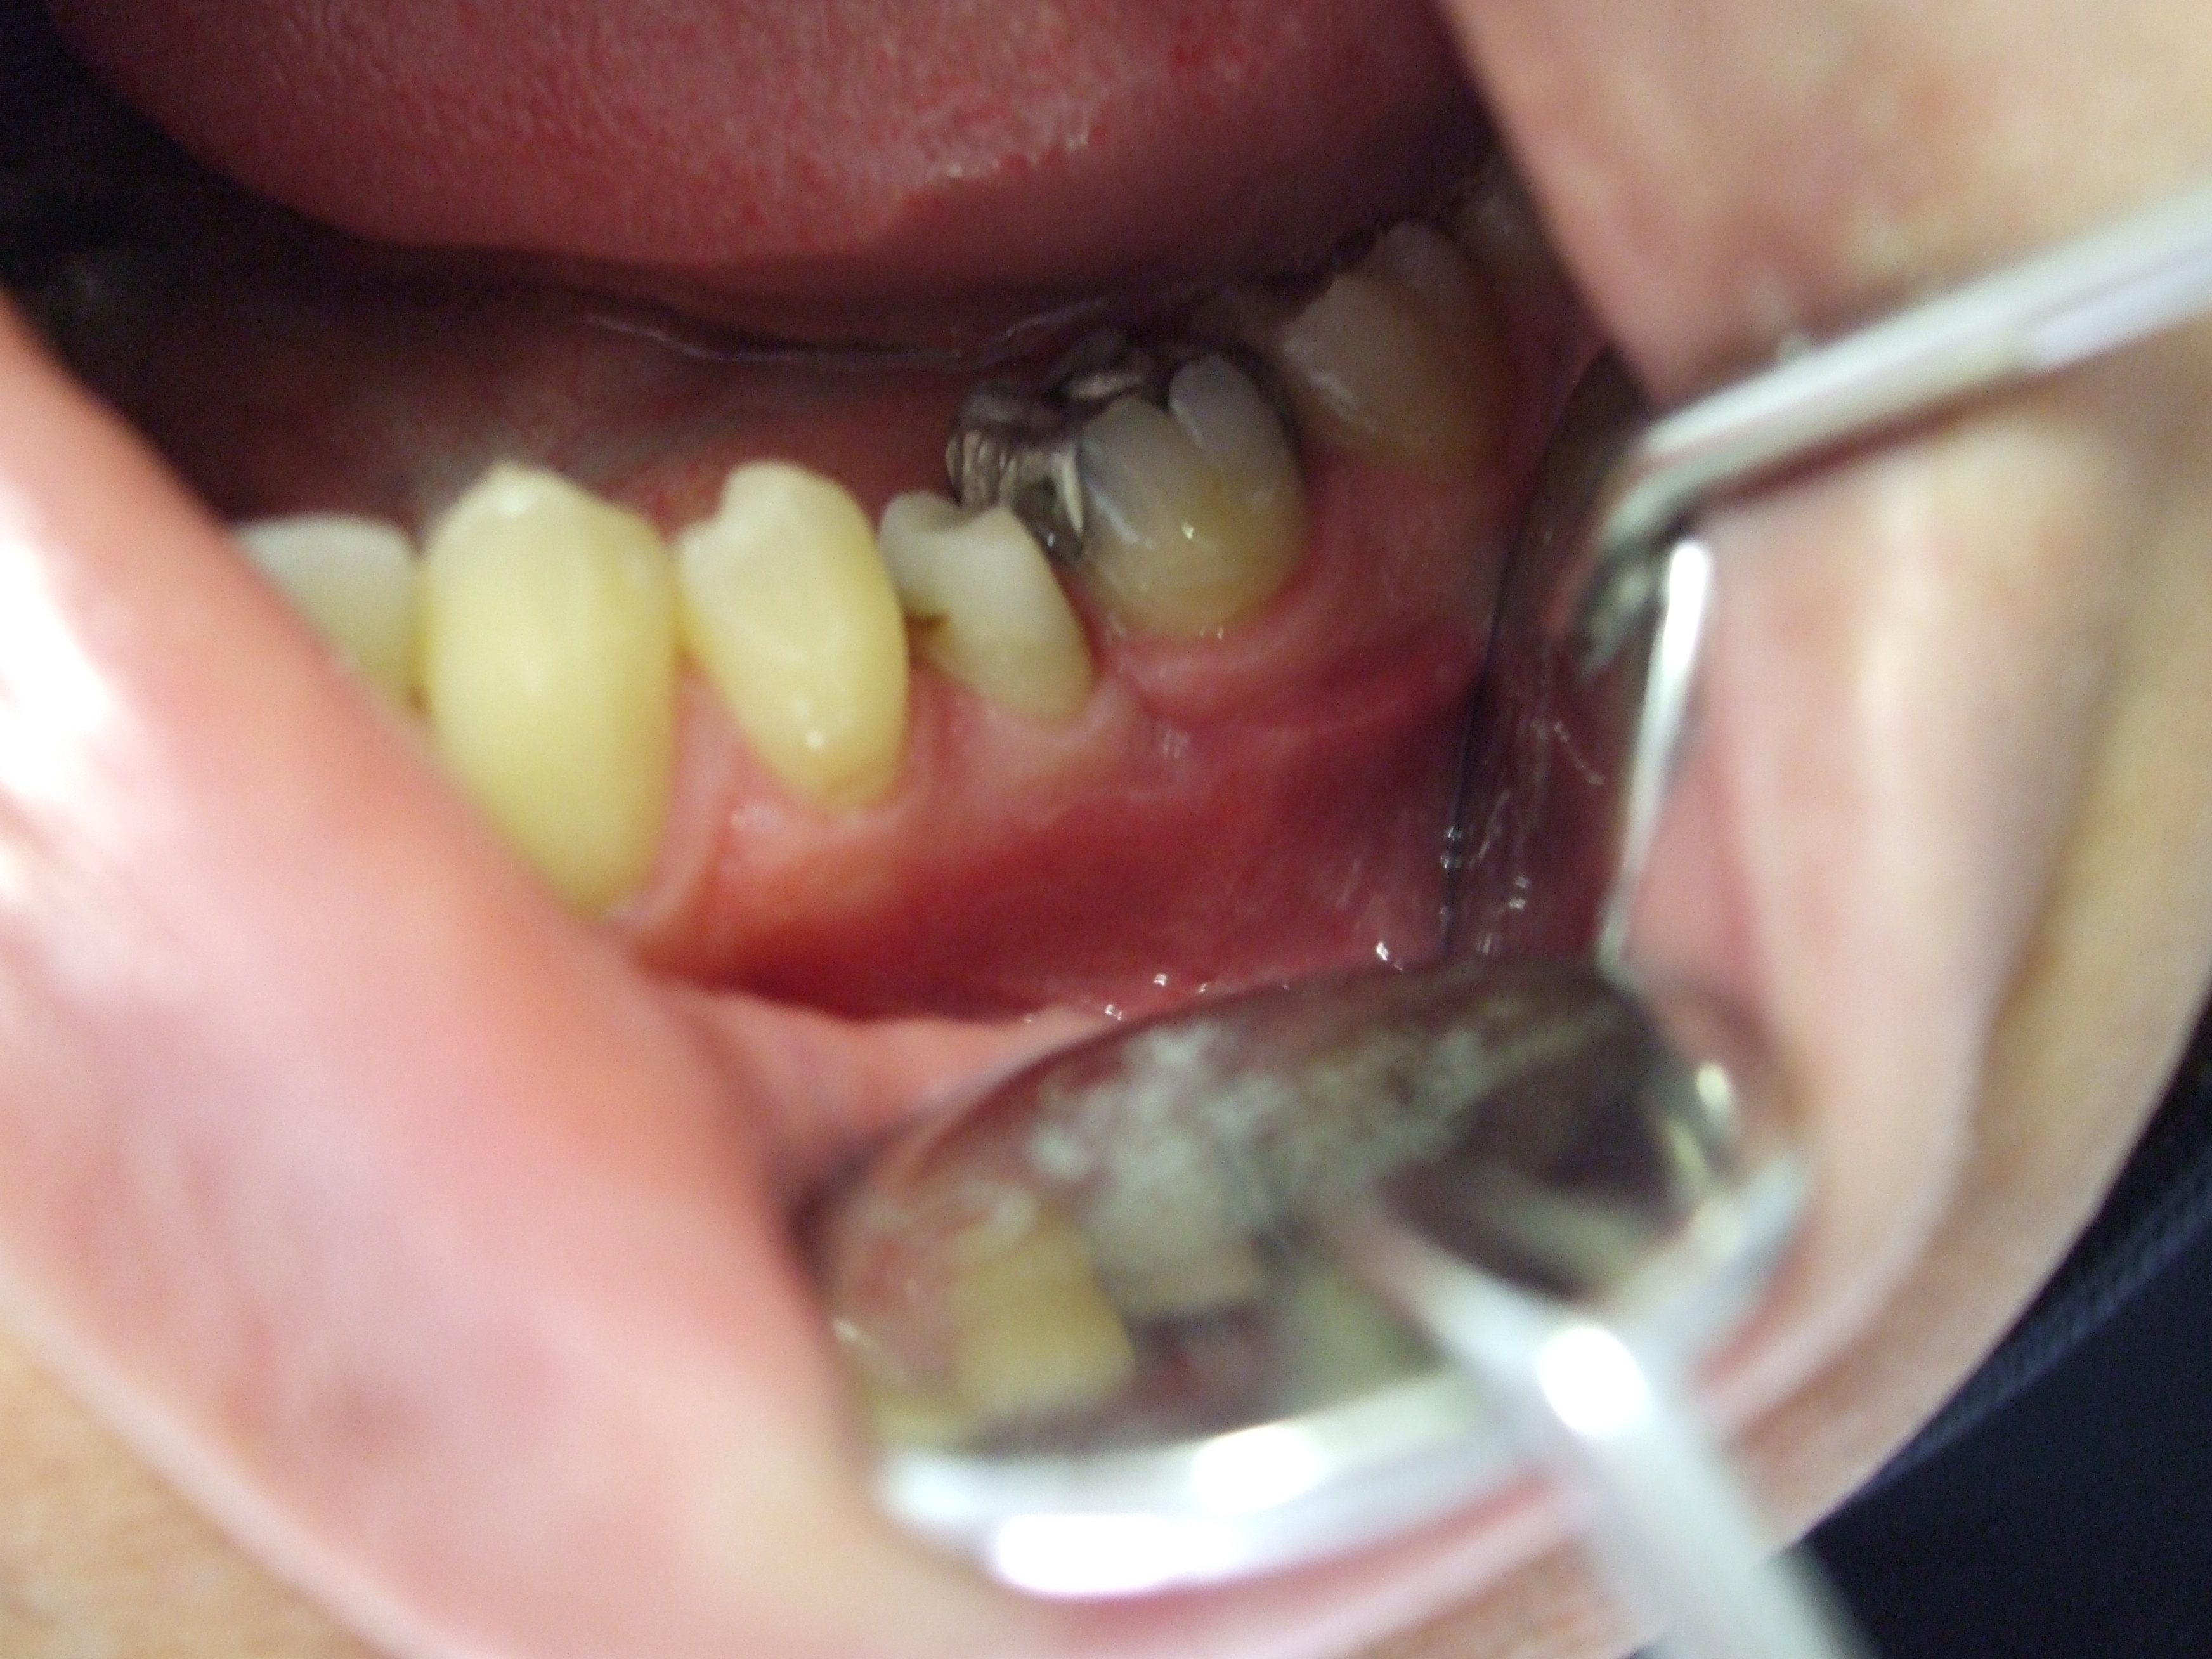

In questo caso clinico la corona del dente era completamente e totalmente distrutta da carie penetrante. Fortunatamente la radice risultava sana ed è stata recuperata con interventi in successione di endodonzia quindi di chirurgia orale (allungamento di corona clinica) ricostruzione del moncone con perni e composito e protesizzazione con corona in ceramica.